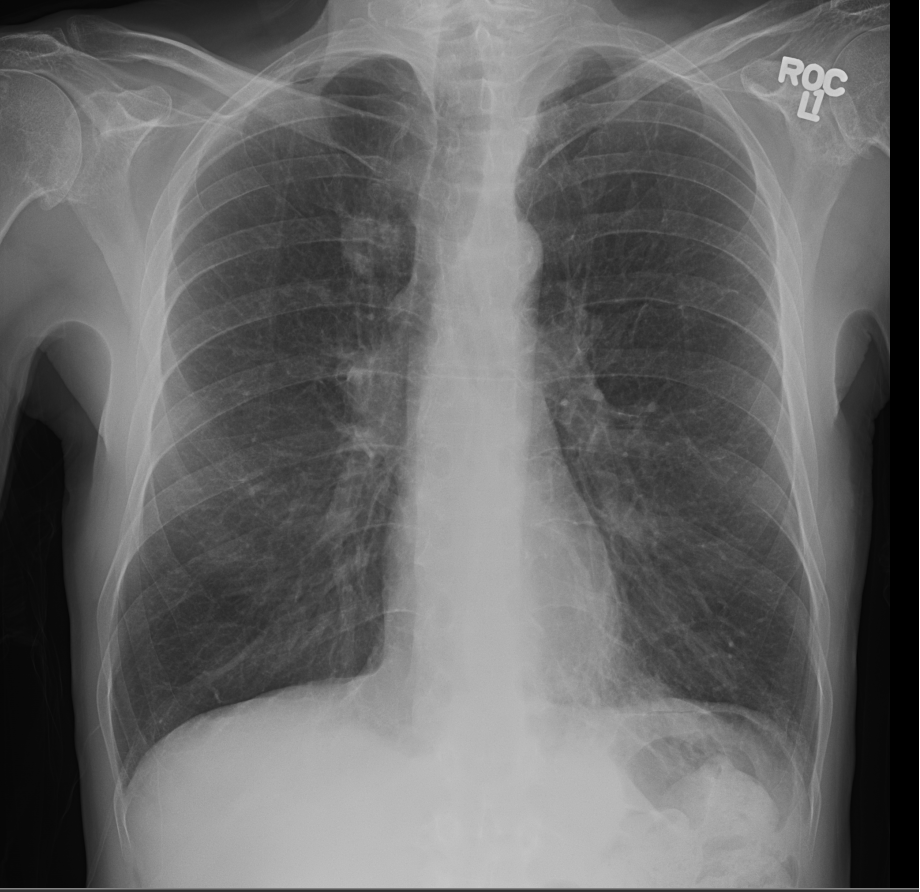

3.3 Applicability to Real X-ray

In order to explore the applicability of our algorithm to real X-ray and to examine whether the enhancement scheme introduces artifacts detrimental to CAD detection performance, we chose to perform the lung enhancement algorithm as a preprocessing step on nodule and mass CAD input images.

To accomplish this, we trained and tested a CheXNet [5] based network on 67,313 images released in ChestX-ray14 dataset(subset of PA images). In Figure 8 we show the results of the enhancement on an image from NIH ChestX-ray14 dataset [4]. The architecture we chose was a DenseNet-121 based network, with 512×512512512512\times 512 input size. Network weights were initialized with pretrained ImageNet weights and training was performed independently for enhanced images and non-enhanced images.

The dataset was split to 44,971 training, 11,245 validation and 11,097 test images. Results are given on the official test set in terms of average precision (AP) for the labels mass and nodule. We see a moderate increase in AP scores for the mass detection task (Table 2).

Refer to caption

(a)

(b)

(c)

(d)

Figure 8: Enhancement result on NIH ChestX-Ray14 image. One network was trained on the original X-ray and a second network was trained on the enhanced X-ray (a) Original X-ray (b) Enhanced X-ray (c) Zoom (d) Zoom -Enhanced